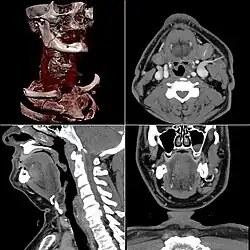

Computed tomography

Computed tomography or CT scan (previously known as CAT scan, the "A" standing for "axial") uses ionizing radiation (x-ray radiation) in conjunction with a computer to create images of both soft and hard tissues. These images look as though the patient was sliced like bread (thus, "tomography" – "tomo" means "slice"). Though CT uses a higher amount of ionizing x-radiation than diagnostic x-rays (both utilising X-ray radiation), with advances in technology, levels of CT radiation dose and scan times have reduced.[9] CT exams are generally short, most lasting only as long as a breath-hold, Contrast agents are also often used, depending on the tissues needing to be seen. Radiographers perform these examinations, sometimes in conjunction with a radiologist (for instance, when a radiologist performs a CT-guided biopsy).